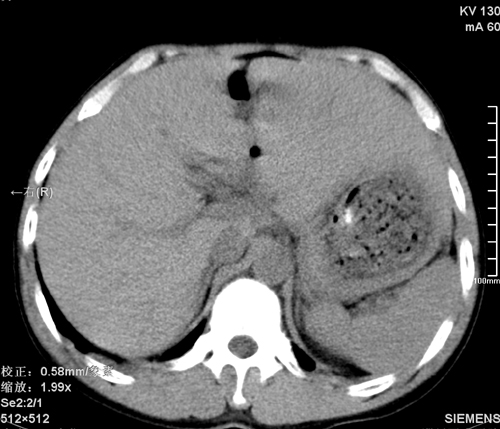

以下是引用tao772在2008-3-28 12:29:00的发言:[br]右侧腹膜后积血,右侧腰大肌挫伤,右侧部分横突骨折. 肾脏最好报一下挫伤,必要时增强。